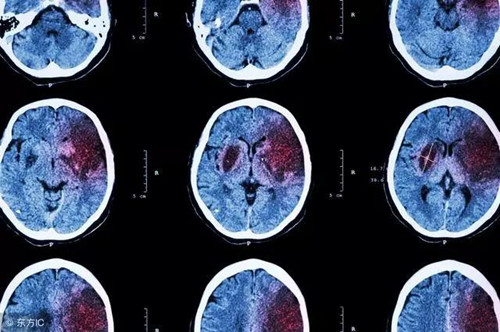

腦梗死和腦溢血都屬于腦卒中,都是情況危急的腦血管病變。我國每年有150萬到200萬的新發腦卒中病例,其中70%是腦梗死,20%-30%為腦溢血。

腦梗死,說白了就是某個腦血管被堵塞了,使得受該血管供血的腦組織迅速壞死,治療后多會留下偏癱的問題。腦溢血則是某個腦血管被血流沖破,但腦組織還能獲得部分供血,因而癥狀相對較輕,治療后也多能完全康復。